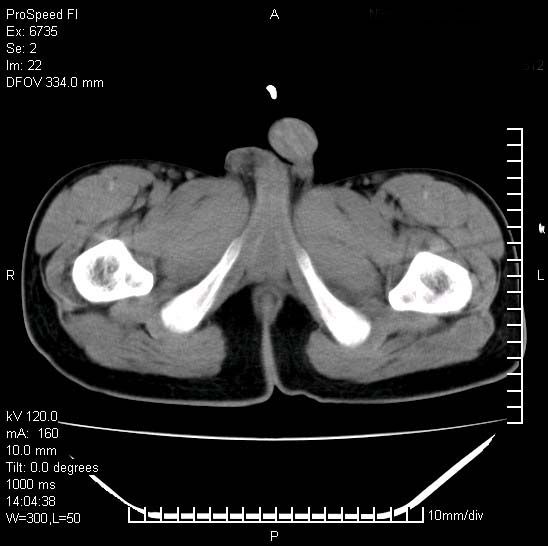

患者自诉胯部疼痛两年余,在当地服用中药,半月前至本院考虑骶髂关节结核,给予抗痨治疗。现发展至右下肢疼痛明显,活动受限,以膝关节处明显,拍膝关节平片无明显异常。

两侧骶骼关节改变,考虑强直性脊炎

左侧骶髂关节面限局性骨破坏,边缘硬化关节腔见钙化物;不出外tb

考虑强直性脊炎,建议查hla-b27

右侧骶髂关节也有类似改变,只是较左侧轻,首先考虑强直性脊柱炎,不除外结核,建议作hla-b27检查。

典型强脊炎改变,髋关节亦有累及

符合强直性脊柱炎表现。